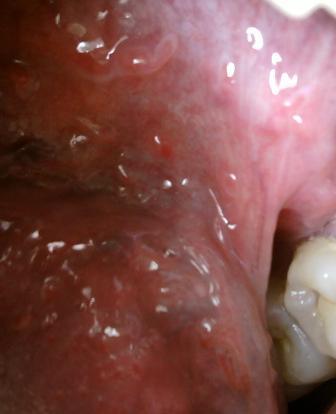

石家庄九州皮肤病医院 > 尖锐湿疣 > > > 尖锐湿疣病人吃什么利于病情的恢复患上尖锐湿疣之后,除了要积极接受治疗之外,在平时的生活中应该多加注意,因为通过合理饮食是可以对于疾病的康复起到一定的缓解效果的。专家温馨提示:尖锐湿疣患者应该少吃辛辣刺激性失去,海鲜也应该少吃。饮食应该以清淡为主。

尖锐湿疣病人吃什么利于病情的恢复现在尖锐湿疣的发病率是比较高的,建议大家患病之后,一定要引起足够的重视,只要及早诊断,采取对症的疗法,从消除病源开始,是可以从根本上遏制病情,患病之后应该多加注意,养成良好的生活习惯是很关键的,不讲究个人清洁卫生,则会导致阴道受病菌感染,从而诱发尖锐湿疣。因此,要求女性勤洗外阴、勤换内裤,以保证清洁。

尖锐湿疣病人吃什么利于病情的恢复尖锐湿疣的饮食对尖锐湿疣术后的保养是非常重要的。戒烟戒酒,因为饮酒会加重病情的发展,导致病情复发。多吃富含维生素的食物。如新鲜的蔬菜、水果及牛奶、鸡蛋等。关于尖锐湿疣的有关知识就先为您介绍到这里,如有任何不理解的可以随时拨打石家庄治疗尖锐湿疣的医院九州皮肤病医院康复热线:0311-89109686和专家取得联系。